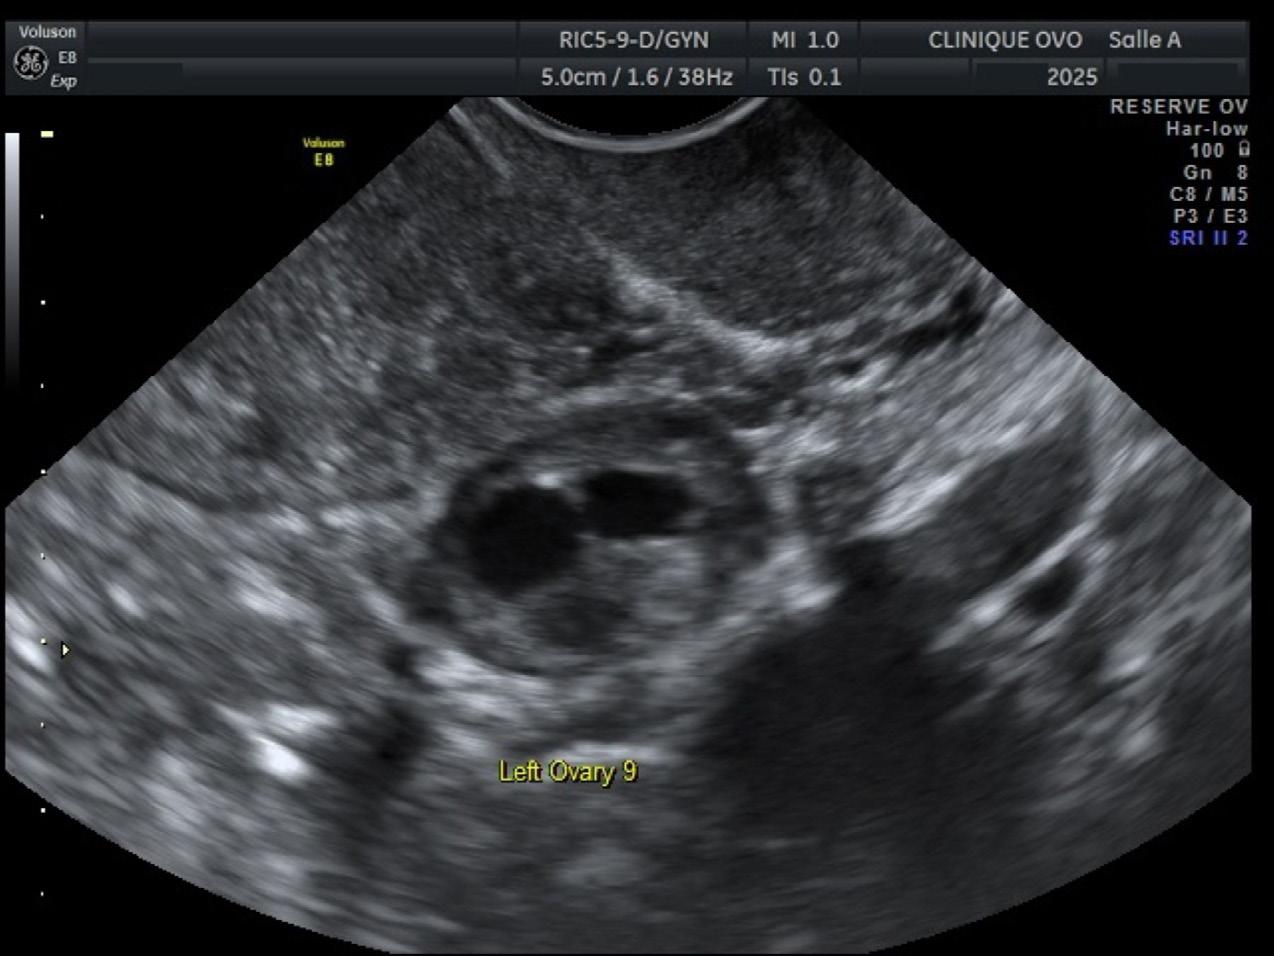

Les femmes naissent avec des millions d’ovules, dont une petite portion est perdue chaque mois6 C’est une mort cellulaire programmée. Plus on avance en âge, plus le bassin d’ovules diminue. En évaluant la cohorte de follicules antraux présents dans les ovules à chaque mois, le médecin peut avoir une bonne idée de la réserve d’ovules dans les ovaires sur le plan cellulaire (Figure 1). L’échographie de réserve ovarienne est faite en début de cycle, entre les jours 2 et 5. Plus on s’approche de l’ovulation, moins on voit de follicules, parce que le follicule dominant prend le dessus, et les autres, plus petits, disparaissent, ce qui pourrait fausser le décompte folliculaire.

Le médecin demande à la patiente de faire faire une prise de sang afin de mesurer son taux d’AMH, pour déterminer si ce que l’on voit à l’échographie correspond à ce qui se passe sur le plan hormonal. En général, la prise de sang devrait être le reflet de l’échographie.